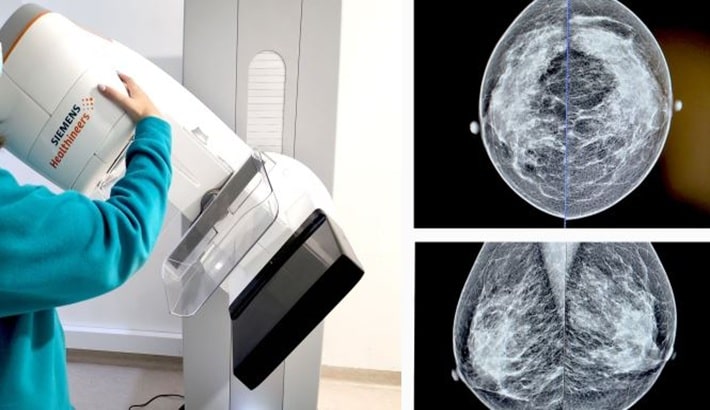

یکی از مهمترین دلایل مراجعه به یک مرکز ماموگرافی مجهز، استفاده از دستگاههای دیجیتال نسل جدید است. این دستگاهها توانایی تولید تصاویر با وضوح بالا را دارند و امکان بررسی دقیقتر توسط پزشک رادیولوژیست فراهم میشود. مرکز تصویربرداری تابا نیز با بهرهگیری از همین تکنولوژی، تلاش کرده است تا بیماران بدون نگرانی از کیفیت نتیجه، برای معاینه مراجعه کنند.

بله. دستگاههای دیجیتال نسل جدید در مقایسه با دستگاههای قدیمیتر، دوز کمتری از اشعه را به کار میبرند. این دستگاهها میتوانند با استفاده از فناوری پیشرفته، تصاویر باکیفیتتری ایجاد کنند در حالی که میزان اشعه کاهش یافته است. به همین دلیل، انتخاب یک مرکز ماموگرافی مجهز اهمیت زیادی دارد. در مرکز تصویربرداری تابا نیز از همین دستگاههای پیشرفته استفاده میشود تا بیمار با کمترین میزان اشعه بهترین نتیجه را دریافت کند.

در گذشته ماموگرافیها با سیستم آنالوگ انجام میشدند که تصاویر کیفیت پایینتری داشتند. اما امروز ماموگرافی دیجیتال امکان بررسی جزئیترین بخشهای سینه را با وضوح بسیار بالا فراهم کرده است. در یک مرکز ماموگرافی که از تجهیزات دیجیتال استفاده میکند، احتمال تشخیص زودهنگام بیماری چند برابر بیشتر است. مرکز تصویربرداری تابا نیز با بهرهگیری از همین تکنولوژی بهروز، توانسته دقت تشخیص را به حد چشمگیری افزایش دهد.

استفاده از دستگاههای دیجیتال پیشرفته

یکی از مهمترین ویژگیهای مرکز تابا، بهرهمندی از دستگاههای ماموگرافی دیجیتال با وضوح بالا است. این دستگاهها قادرند کوچکترین تغییرات در بافت سینه را ثبت کنند و امکان تشخیص زودهنگام بیماری را فراهم آورند.

برخلاف مراکز قدیمی که همچنان از دستگاههای آنالوگ استفاده میکنند؛ تابا با بهروزرسانی مداوم تجهیزات خود توانسته دقت نتایج را به بالاترین سطح برساند.